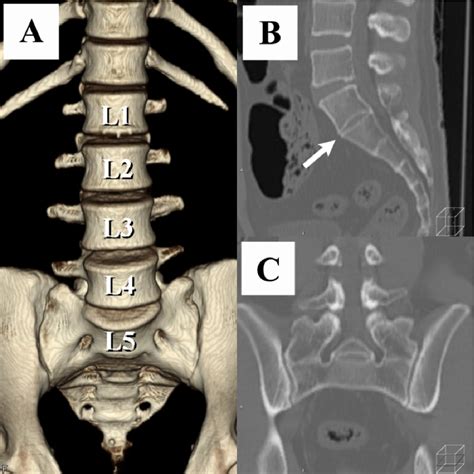

Diagnostic Imaging and Identification

Radiology plays the most critical role in diagnosing Transitional Lumbosacral Anatomy. Standard X-rays of the lumbar spine are often the first step, but they may not provide enough detail to distinguish between a fusion and a complex articulation. In more complex cases, Computed Tomography (CT) scans or Magnetic Resonance Imaging (MRI) are utilized to provide a three-dimensional view of the lumbosacral region.

Radiologists utilize a method called vertebral counting, starting from the C2 vertebra in the neck and moving down through the thoracic spine to determine the exact level of the LSTV. This rigorous process ensures that the patient's anatomy is correctly mapped, preventing miscommunication between the imaging department and the orthopedic surgeon.